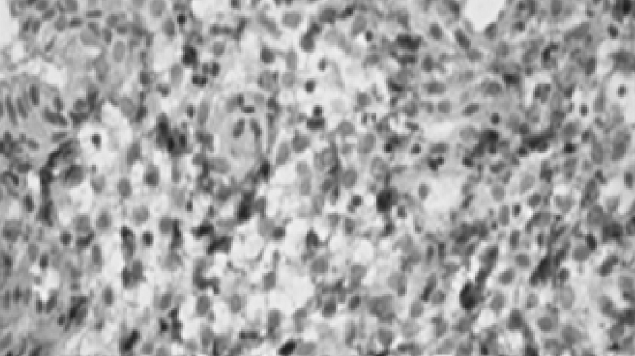

Согласно иммуногистохимическому заключению экспрессия эстрогеновых и прогестероновых рецепторов в эндометрии соответствует фазе менструального цикла (рис. 3). Выявляются признаки хронического воспаления (хронический эндометрит) со слабым аутоиммунным компонентом (рис. 4–10).

Рис. 4. Очаговая лимфоцитарная и нейтрофильная инфильтрация стромы эндометрия при увеличении объектива ×400